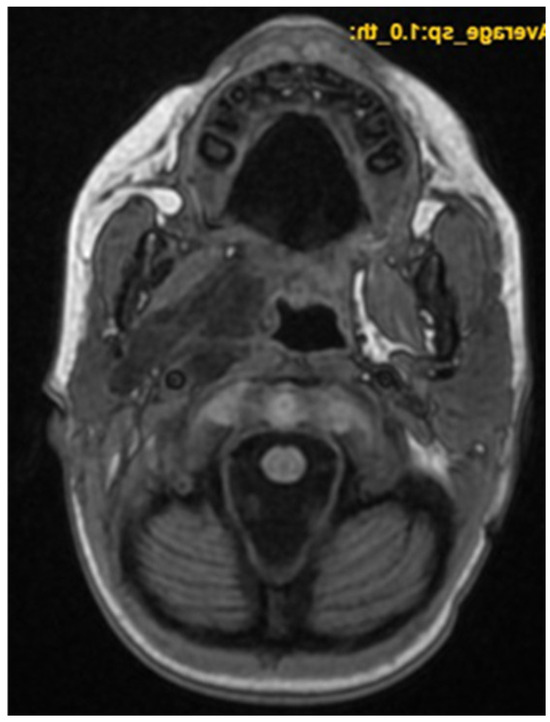

A CNS MRI was performed, which reveal a large lobulated formation in the oropharynx and nasopharynx with left tonsil involvement, spreading to the retropharyngeal space and propagating through the left Eustachian tube into the middle ear. The previously formed surgical cavity was completely infiltrated from the soft tissue tumour mass. Approximate dimensions of the lesion in the mastoid—25/45 mm. axial, 38/39 mm. coronal (Figure 6, Figure 7 and Figure 8).

Figure 6. MRI of the patient on postoperative day 17.

Figure 7. MRI of the patient on postoperative day 17.

Figure 8. MRI of the patient on postoperative day 17.